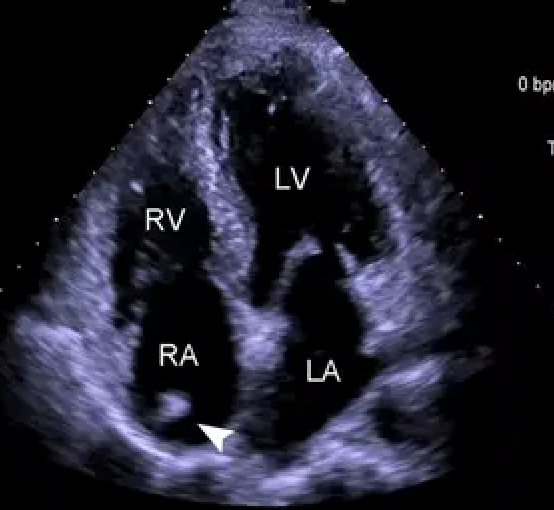

心脏彩超

超声心动图

主要检查心脏各结构的解剖、位置、大小、形态与血流动力学是否正常,能测定心功能是否正常,了解心脏有无结构异常、房室大小异常,有无瓣膜病变、血流方向和速度异常,有无肿瘤、心包异常积液等。

能排查常见的疾病如高血压性心脏病、肺源性心脏病、风湿性心脏病、心功能不全、心脏瓣膜疾病(发育畸形、狭窄、关闭不全、脱垂、钙化、赘生物等)、升主动脉瘤/夹层、先天性心脏疾病(房缺、室缺、动脉导管未闭、肺动脉瓣狭窄等)、心肌病变(肥厚性心肌病、扩张性心肌病等)、心脏/心包肿瘤(粘液瘤、脂肪瘤等)、心包积液等。